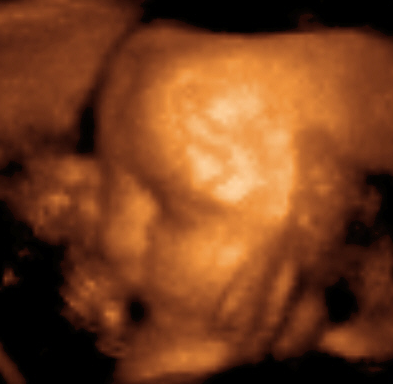

산과용 초음파는 어떤 조건이 산모와 태아에게 유해한지를 확인하는 데 이용된다. 건강관리 전문가들은 이러한 상황을 진단하지 않았을 때의 위험이 초음파 영상 검사의 위험보다 훨씬 큰 것으로 판단한다. Cochrane Review에 따르면, 조기 임신 기간(24주 이전)에 주기적인 초음파 진단이 임신 기간 판단, 다태 임신과 임상학적으로 알려지지 않은 태아 기형을 조기에 발견하는데 도움이 되는 것으로 나타났다.임신 기간 동안 산과 진료에 정기적으로 사용되는데, 초음파 영상을 이용해 다음 사항을 확인할 수 있다.

- 태아의 생존 및 발달 상태 확인

- 태아의 움직임과 심장박동 확인